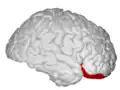

Orbital gyrus shown in red.

Lateral orbitofrontal cortex